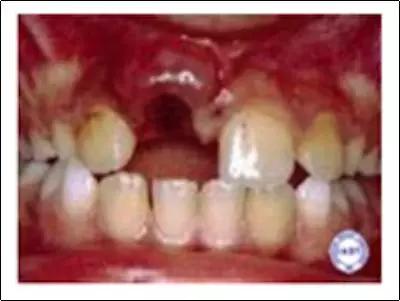

② 牙齿嵌入

如果发生牙外伤后,似乎有牙齿缺失,但又无法找到不见的牙齿,那么有可能是被推到了牙龈里,而且口腔局部出血和肿胀使这颗牙更难被看到。